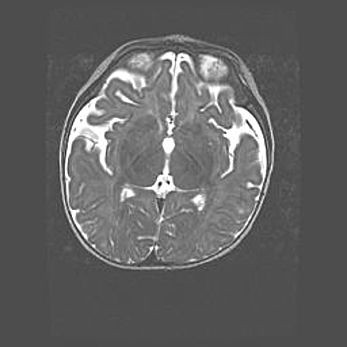

Лейкомаляция с кистозно-глиозной дегенерацией головного мозга.

Возраст: 2 месяца 25 дней

Вес: 6400 г

Окружность головы: 40 см

Срок гестации: 41 неделя

Лейкомаляцию относят к ишемически-гипоксическим повреждениям головного мозга, диагностируемым у новорожденных. При лейкомаляции в головном мозге обнаруживают очаги некроза, возникшие после тяжелой гипоксии и нарушения кровотока. В процессе морфогенеза очаги проходят три стадии: 1) развития некроза, 2) резорбции и 3) формирования глиозного рубца или кисты. Перивентрикулярная лейкомаляция (ПЛ) встречается примерно в 12% случаев среди новорожденных, обычно – у недоношенных детей, причем, частота ее зависит от массы, с которой младенец появился на свет. Наибольшее число малышей страдает лейкомаляцией, если масса при рождении 1500-2500 г.